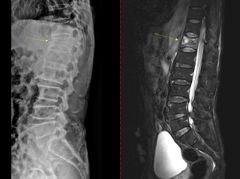

대다수 사람들은 '류마티스'를 비 오기 전 쑤시는 무릎이나 노화로 인한 퇴행성 관절염으로 떠올리기 쉽다. 하지만 의료계는 류마티스 질환은 단순히 관절이 닳아서 생기는 병이 아니라고 설명했다. 최인아 고대구로병원 류마티스내과 교수의 도움말로 류마티스에 대해 알아본다. 28일 의료계에 따르면 류마티스 질환은 관절과 연골은 물론 뼈, 근육, 인대 등을

송종호기자2026.02.28 16:01:00